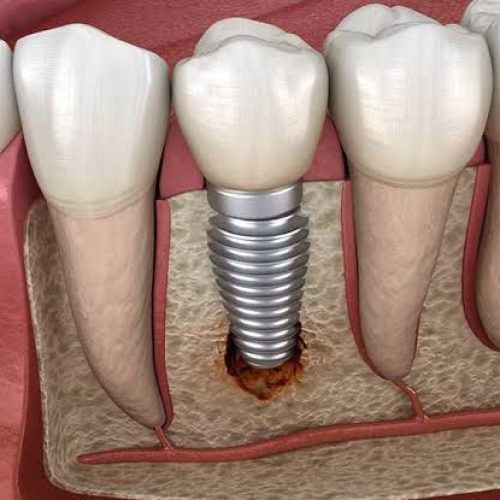

1. Infection:

After getting a dental implant, it is very important to take care of your oral hygiene. The most common problem with dental implants is infection during treatment. It can be treated with the help of anti-biotics and painkillers provided by your dentist

2. Receding gums or gum recession:

Gingival recession is also one of the main complications faced by a person after getting an implant. Recession of the gums at the site of the implant occurs if oral hygiene is not maintained. To prevent receding gums, the patient should maintain their oral hygiene properly and visit their dentist for regular check-ups.

3. Loose Dental Implant:

Osseointegration is the process by which a dental implant fuses with the bone. If this process of osseointegration fails, the implant placed becomes loose and fails. There is nothing you can do about it. Sometimes implants don’t integrate with the bone and even dentists cannot tell you the exact reason.